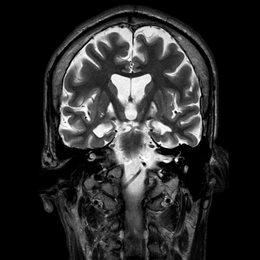

Burke-Fahn-Marsden rating scale26 (BFMRS) score was: 104/120. A T2 weighted brain Magnetic Resonance imaging (MRI) scan showed hypersignal bilaterally involving both pallida, mostly affecting the most medial part (Figure 2). Treatment attempts with Trihexyphenidyl, Carbidopa-Levodopa, Carbamazepine, Clonazepam, Phenytoin and Baclofen were unsuccessful. Botulinum toxin injections provided some relief of the muscular contractions but rapidly became ineffective considering the importance of dystonic movements. The family gave informed consent for DBS surgery. As the main output of the pallidum is the ventrolateral thalamic nuclei (Voa) and the centromedian-parafascicular nucleus,30,34 we decided to target Voa for DBS and hoped it would act directly on the last distal part of the retroactive feedback to the motor cortex from GPi.

Figure 2 Pre-operative MRI showing selective necrosis of the Globus Pallidus interna, predominantly on the right side (above images are in radiological view).